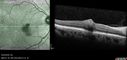

Perifoveal Microaneurysm - Not Diabetic (also reticular pseudodrusen)359 views87 year old female with fluctuating macular edema in the right eye from a perifoveal MA. (no treatment). VA 20/40 OUApr 02, 2020